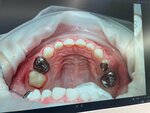

Dental clinic Da Vinci, Khabarovsk, photo